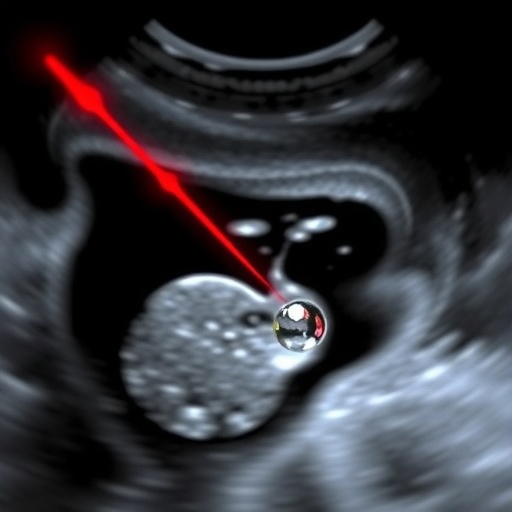

Central to this technology are nanodroplets—tiny, engineered particles designed to respond to specific light frequencies. Unlike conventional ultrasound contrast agents, these nanodroplets remain inert under regular imaging, only transitioning to highly echogenic microbubbles upon laser stimulation. When exposed to finely tuned laser pulses, the nanodroplets rapidly vaporize, expanding into microbubbles that scatter ultrasound waves with much greater intensity. This transformation dramatically amplifies the ultrasonic signal, thereby allowing for precise localization of these agents in the body.

What makes this technique revolutionary is its ability to provide spatial resolution beyond what was previously achievable by ultrasound alone. By synchronizing laser activation and ultrasound detection, the researchers were able to capture the exact moments when nanodroplets convert to microbubbles, effectively creating a map of targeted structures with micrometer-scale precision. The heightened contrast and resolution make it possible to visualize minute biological features, including cellular-level vessel structures and microenvironmental changes, which were previously undetectable using standard ultrasound methods.

In experimental validations, the researchers demonstrated the efficacy of PAULI in imaging complex tissue phantoms and in vivo models with striking results. The images obtained exhibited markedly enhanced contrast-to-noise ratios and spatial detail compared to conventional ultrasound methods. This advance suggests potential for early disease detection, such as identifying microtumors or vascular abnormalities long before they manifest symptomatically or become visible through standard imaging modalities.